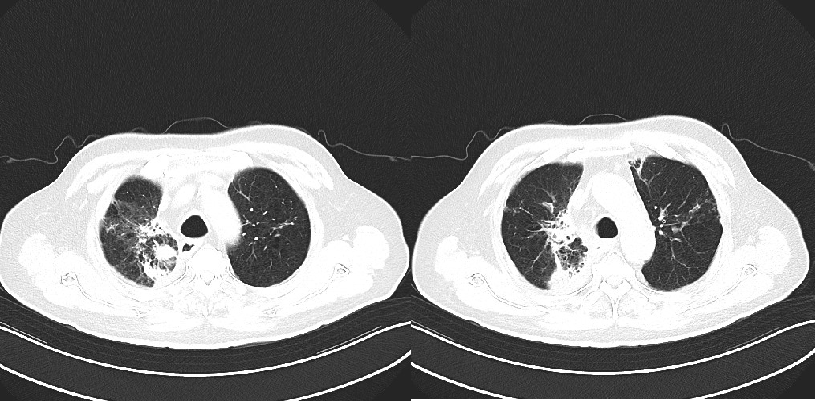

2022年3月,患者至外院住院,拒绝手术,常规口服卡培他滨化疗+右肺病灶放疗(DT 5Gy×11f)。2022-3-30来院复查胸部CT(图2)提示稳定。

2022年5月,患者因咳嗽、气喘来院复查CT(图3)示:放射性肺炎,给予激素、抗炎、平喘等治疗后好转。后多次因肺炎入院给予抗炎、激素、平喘等治疗。

2023年4月,复查胸部CT(图4):符合右肺上叶病变治疗后复查表现,右肺下叶及左肺上叶纤维灶、结节灶,邻近支气管扩张;COPD影像表现,左侧肾上腺结节;右肺上叶肿瘤局部进展。

2023年9月16日,患者因气喘,复查胸腹部增强CT(图5):符合右肺上叶病变粒子植入表现、符合右肺下叶及左肺上叶纤维灶、结节灶,邻近支气管扩张、COPD,左侧肾上腺结节。痰培养:铜绿假单胞菌。后多次因肺炎给予抗炎治疗。

2024年4月,查胸部强化CT(图7):符合右肺上叶病变粒子植入表现,较前略增大;符合右肺下叶及左肺上叶纤维灶、结节灶,邻近支气管扩张;COPD、右侧胸腔积液、左侧肾上腺结节较前大致相仿。患者家属拒绝再次活检及静脉化疗。

经MDT会诊,给予 “长春瑞滨软胶囊40mg tiw+重组人血管内皮抑制素210mg civ72h”治疗。5周期,影像学检查右肺肿瘤缩小,患者无胃肠道反应(图8),血常规检测无骨髓抑制(图9)。

2024年9月7日,复查胸部CT(图11):1.符合右肺上叶癌粒子植入表现。2.符合左肺上叶纤维灶、结节灶,邻近支气管扩张复查表现。3.右下肺纤维灶。4.符合COPD影像表现。5.左侧肾上腺结节。